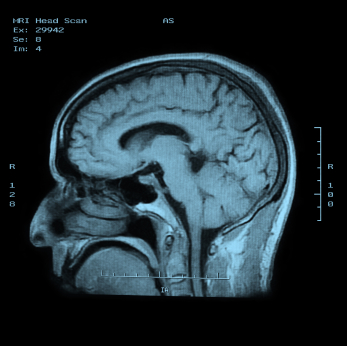

Изучение истории болезни и медицинский осмотр не проводятся. Следующие испытания проводятся для подтверждения диагноза: EMG, антитела рецептора ацетилхолина, и / или Tensilon (эдрофоний) тест. КТ или МРТ может быть сделано для поиска тимуса опухоли (опухоль вилочковой железы).